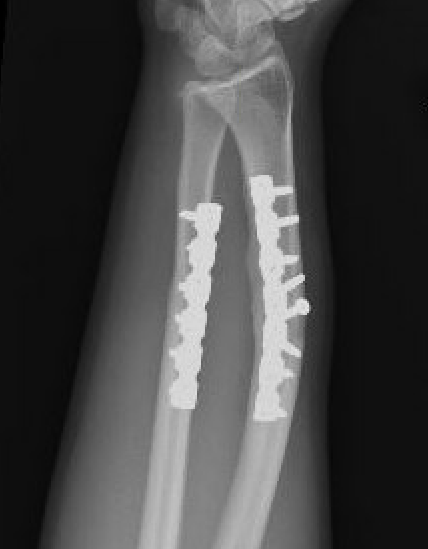

Radial malunion / Non anatomical ORIF of BBFF

Radial malunion after ORIF of BBFF

Etiology

Non operative management of BBFF

Non anatomical ORIF of BBFF